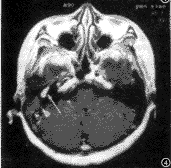

图3 左侧颈静脉球瘤,横轴位T2WI示左侧颈静脉孔区病灶,近等信号(黑箭),其内可见流空,病灶外侧另见高信号的乳突积液(箭头)